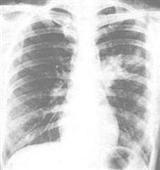

X線顯示肺部有形態多樣的浸潤影,呈節段性分布。外周血白細胞計數輕度增高。痰、鼻分泌物及咽喉拭子培養出肺炎支原體可確診。

支原體肺炎患者胸部X線檢查變化很大,病變可很輕微,也可很廣泛。體徵輕微而胸片陰影顯著,是本病特徵之一。血常規檢查白細胞高低不一,大多正常,有時偏高。

輔助檢查(一)X線胸片為肺紋理增多,肺實質可有多形態的浸潤形,以下葉多見也可,呈斑點狀,斑片狀或均勻模糊陰影約1/5有少量胸腔積液。